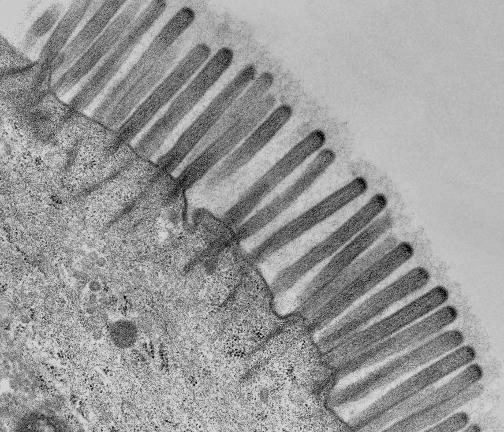

Иллюстрация к книге — Взламывая анатомию [image209.jpg]

Кишечные ворсинки встречаются в тонком и толстом отделах кишечника, который выстлан эпителиальными клетками (энтероцитами), образующими «щеточную кайму».

Иллюстрация к книге — Взламывая анатомию [image210.jpg]

Микроворсинки – это микроскопические выступы плазматической мембраны клеток, выстилающие поверхность ворсинок. Микроворсинки еще больше увеличивают площадь всасывания. Можно заметить, как из цитоплазмы выступают микрофиламенты.